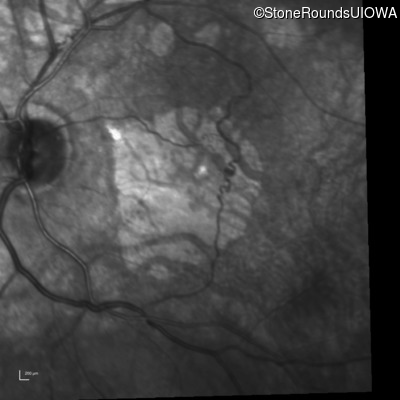

Infrared Fundus Photograph - Right - 20/100

Exemplar

Infrared Fundus Photograph - Left - 20/100